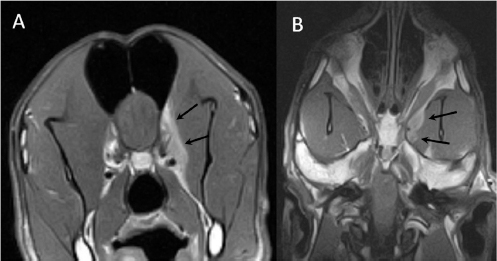

A 3-year-old female Great Dane was referred for acute onset behavioral changes (aggression and disorientation) of 2 weeks duration, and seizures from 24 hours prior to presentation. Physical examination revealed no abnormalities in body temperature, body condition score, heart rate, pulse quality, or cardiopulmonary auscultation. All lymph nodes were considered of normal size and no pain was elicited upon manipulation of the orbital, aural, or cranial musculature. Neither was there any history of dermatological or traumatic lesions in the eye, ear, or mouth. The neurological examination revealed the patient to be obtunded with decreased postural reactions and menace response worse in the left side. Neuroanatomic lesion localization was considered focal in the right prosencephalon with a possible increase in intracranial pressure. Hematological and serum biochemical analysis showed no abnormalities. Magnetic resonance imaging was performed using a low-field magnet (Airis Mate; Hitachi, Tokio, Japan). The study revealed a left-sided single frontal intra-axial lesion affecting gray and white matter adjacent to the internal capsule at the level of the optic canal (Fig. 1). The lesion presented signal homogeneity characterized by hyperintensity on T2W and FLAIR sequences and hypointensity in T1W sequences with peripheral enhancement after intravenous contrast administration (Fig. 1A and 1B). The lesion had a round shape with the greatest diameter of 2.84 cm. This enhancement was also recognized in the surrounding meninges following the brain surface following sulci. A small linear tract observed was directed dorsally from the lesion through the corona radiata (Fig. 1B). The lesion was associated with extensive perilesional vasogenic edema that worsened the mass effect characterized by a midline shift. The orbital and medial pterygoid muscles also showed an intense enhancement (Fig. 2). The wing of the presphenoid bone was thinner than the contralateral bone (Fig. 1B). A CT scan (Astelion 16, Toshiba, Tokio, Japan) was performed after MRI that allowed the identification of osteolysis in the presphenoid bone immediately dorsal to the orbital fissure (Fig. 1C). CT scan also revealed a hypoattenuating intra-axial lesion located in the left frontoparietal lobe together with diffuse hypoattenuation of tissues adjacent to the left optic nerve and the left pterygoid muscle. Finally, CSF analysis showed no abnormalities. On the basis of advanced radiological findings, the main differential diagnosis was an intracranial abscess due to the extension of the extracranial septic process through presphenoid bone. Because of rapid neurologic deterioration and suspected increased intracranial pressure, surgical excision was planned. A modified left rostrotentorial craniectomy was performed. Temporalis muscle and fascia were retracted, extending the incision cranially through the temporal line. Once the frontal and presphenoid bones were exposed an area of osteolysis was observed in the wing of the presphenoid bone immediately dorsal to the orbital fissure. The craniectomy (approximately 3 cm diameter) was centered on the osseous defect. A mucopurulent discharge presented immediately after the incision of the dura mater. A sample was collected for its microbiological study. The surgical site was flushed with sterile saline revealing the tip of a grass awn which was extracted from the brain parenchyma together with a small amount of purulent fluid (Fig. 3). After extensive flushing, the meninges were left open to allow drainage and the incision was closed as per routinely. Postoperative CT showed the correct location of the craniectomy and resolution of the abscess which was substituted by gaseous content but remained inside and on the dorsal surface of the frontal lobe (Fig. 4). Immediate postoperative therapy consisted of amoxicillin + clavulanic acid (Synulox 500, Zoetis Spain SL) 22 mg/kg PO, q8h; marbofloxacin (Marbocyl P80, Vetoquinol SA) 5 mg/kg PO, q24h; metronidazole (Flagyl 250, Sanofi-aventis SA) 15 mg/kg PO, q12h; prednisone (Prednisona Kern Pharma 30mg, Kern Pharma) 0.5 mg/kg PO, q12h; tramadol (Tramadol retard Combix 100 mg, Laboratorios Combix S.L.U) 2 mg/kg PO, q8h; famotidine (Famotidina Normon 40 mg; Laboratorios Normon SA) 0.7 mg/kg PO, q24h; and phenobarbital (Phenoleptil 100 mg, Le Vet BV) 2.5 mg/kg PO, q12h. Cultured samples were positive for Pseudomonas aeruginosa sensitive to ciprofloxacin, imipenem, and amikacin among other antibiotics. Based on these results, antibiotic therapy was changed to ciprofloxacin (Ciprofloxacino 500, Laboratorios Normon SA) 10 mg/kg PO, q12h and metronidazole 15 mg/kg PO, q12h for 2 months. Prednisone, tramadol, and famotidine were withdrawn and phenobarbital was maintained at 2.5 mg/kg q12h. Six-month post-operative revision magnetic resonance revealed no signs suggesting the existence of an inflammatory process (Fig. 5). In the area where the abscess had been located, a fluid-filled cavity suggesting being CSF was observed. One year follow-up revealed the patient had seizures every 3 months with neurological examination remaining normal. The patient died 2 years later of unrelated causes.

Fig. 5. (A) Transverse T2-weighted, (B) transverse post-contrast T1-weighted image, and (C) dorsal post-contrast T1-weighted image obtained 6 months after surgery. Note the absence of any contrast enhancement and residual lesion connecting the lateral ventricle (arrows). Also, note the defect in the presphenoid bone (arrowheads in C).

This case represents the only case in which long term (6 months) radiological follow-up of the lesion was carried out by means of MRI, proving the disappearance of the lesion. The seizures that the patient had during the rest of its life were probably due to epileptogenic focus in the cerebral parenchyma where the abscess was located.